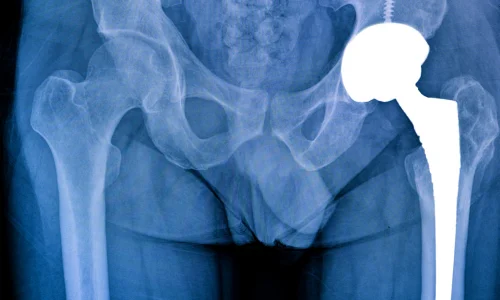

Damaged hip joint surfaces are replaced with artificial implants to relieve pain, improve mobility, and restore smooth movement. Ideal for severe arthritis and long-term comfort.